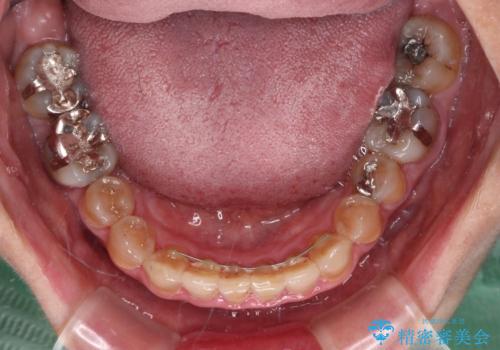

- 前歯のデコボコと、顎に負担のかかる歯並びを改善したいとのことで来院された患者様です。

うまく歯ぎしりができず、強く食いしばりをしてしまう咬み合わせであったため、奥歯に非常に負担がかかっていました。

インビザラインを用いて前歯のデコボコを改善するとともに、奥歯の咬み合わせを変えてスムーズに歯ぎしりできるように排列していくこととしました。